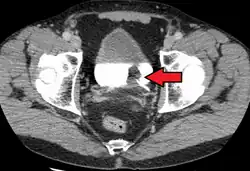

Transitional cell carcinoma of the bladder. The white in the bladder is contrast.